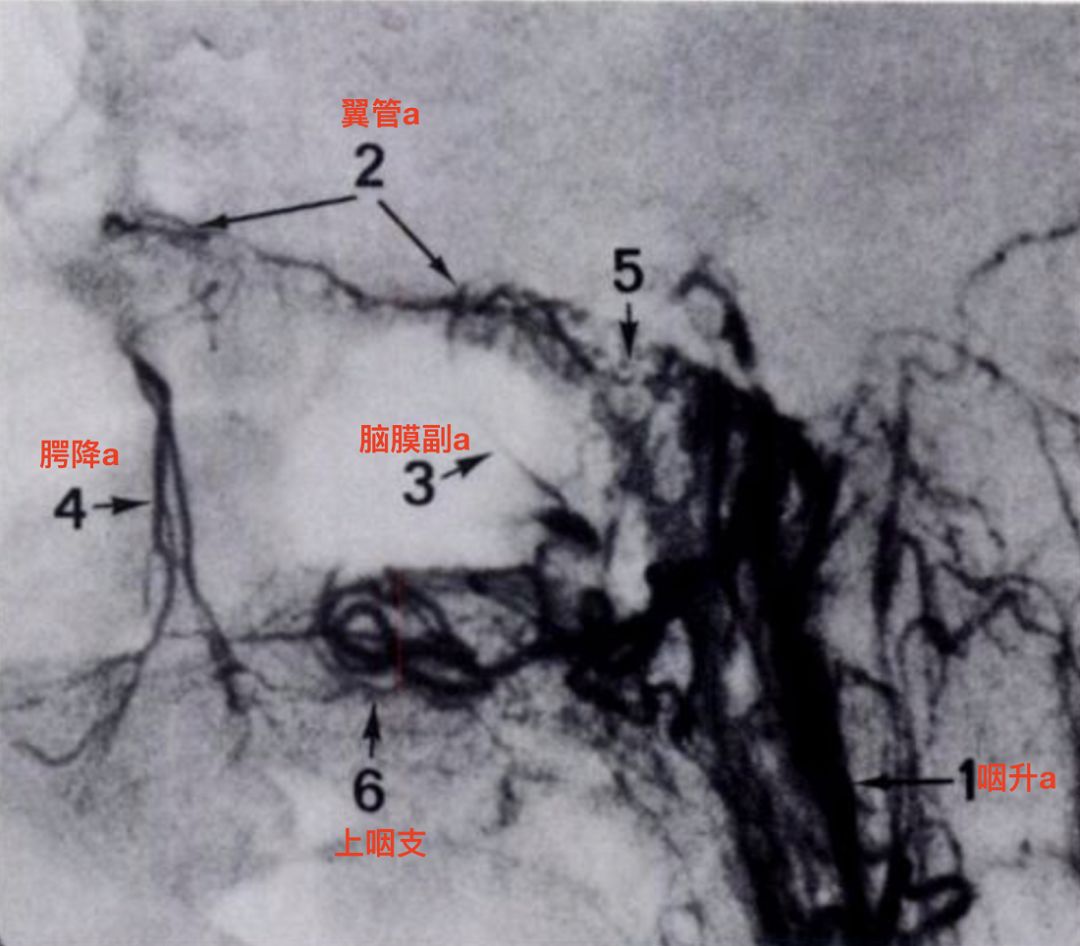

选择性咽升动脉造影,侧位,晚期(Osborn, 1980)。可见翼管动脉,脑膜副动脉,咽升动脉和腭降动脉之间的吻合。此处软腭部分也由咽升动脉供血,一般此处由面动脉的腭升动脉供血。